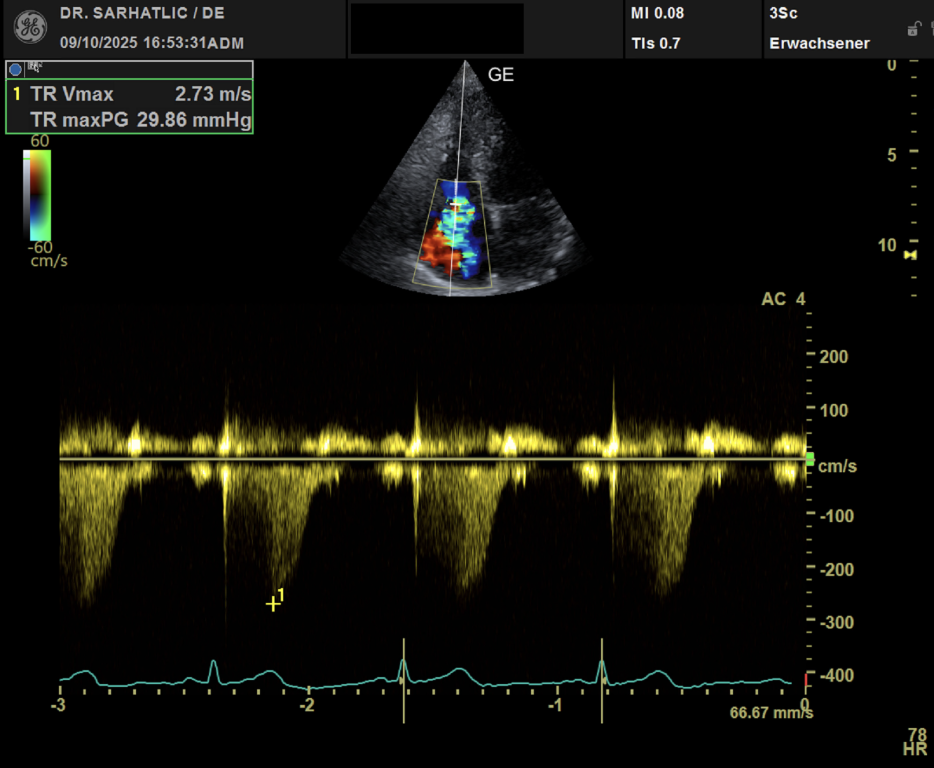

- Ultraschall des Herzens (Echokardiografie)

HERZRHYTHMUS- UND KREISLAUFDIAGNOSTIK- Herzrhythmusanalyse mit exzellenter Signalqualität

VORSORGE-SCHWERPUNKTE- Herz- & Kreislauf-Vorsorge

- Schlaganfallvorsorge (inkl. Gefäßdiagnostik)